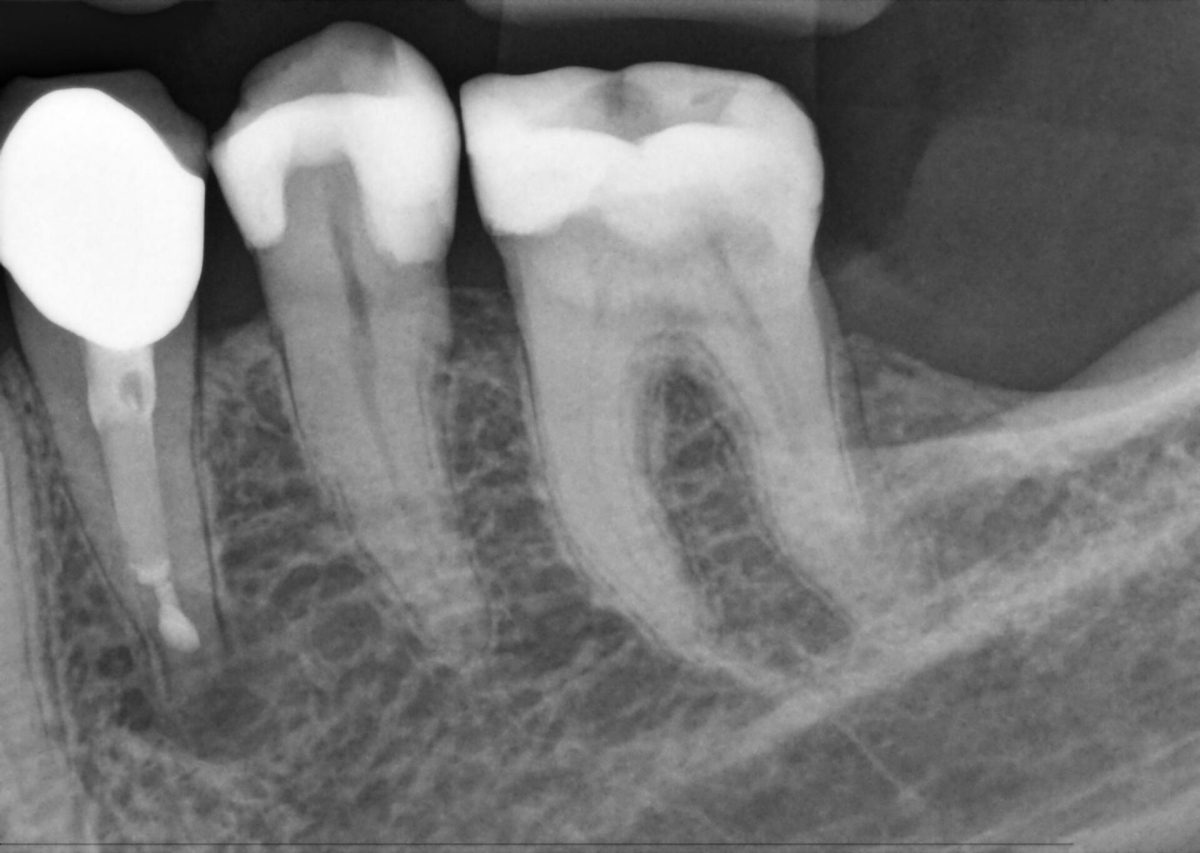

Xios AE - galerie ukázkových snímků

Zvýšená citlivost senzoru a rozšířené spektrum expozice optimalizované pro nízkou dávku umožňuje optimální viditelnost a stanovení diagnózy při snížené dávce záření. Podexponované snímky jsou úspěšně vyvážené, je zachována konzistentní kvalita obrazu a flexibilita dávky.